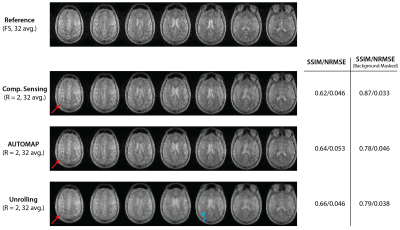

Human brain images from a 22-minute scan are shown in Figure 4. Aliasing artifacts are present in all reconstructions of the 2$$$\times$$$ undersampled data. The Unrolling network appears to suppress noise within the brain itself.

Figure 4: Images of the human brain acquired at 6.5$$$~$$$mT. Metrics for CS, AUTOMAP and Unrolling reconstructions of $$$R~=~2$$$ data are calculated against the fully sampled (FS, 22-minute) scan acquired with 32 averages. The central 7 of 25 slices are shown. Red arrows indicate aliasing artifacts present in all reconstructions due to undersampling. The blue arrow indicates a region in which a denoising effect most present in the Unrolling reconstruction can be observed.